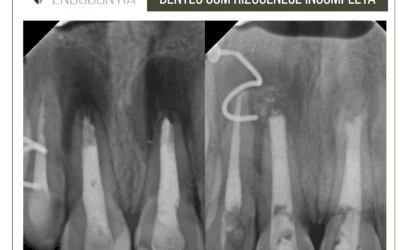

Paciente procurou atendimento para o tratamento endodôntico do dente 41 indicado por outro colega. Não apresentava sinais e sintomas e no exame clínico, dor à palpação e teste térmico negativo no dente 41. No exame radiográfico, imagem radiolúcida circunscrita no referido dente. Verificou-se na exploração dos canais, que o dente tinha mais de um canal. Após o tratamento e medicação com hidróxido de cálcio, o paciente só retornou após 8 meses, e o exame radiográfico revelou imagem de reparação.

Foi realizada então a irrigação e obturação. Observa-se uma anormalidade anatômica, com presença de canais colaterais.

Em virtude do achatamento no sentido mesiodistal, canais de incisivos inferiores tendem a ser mais amplos na direção contrária (vestibulolingual). Por esse motivo, a instrumentação não consegue contemplar todas as suas paredes, o que resulta em canais deficientemente instrumentados, limpos e obturados. Ainda, esse achatamento pode predispor à ocorrência de dois canais, um vestibular e um lingual, nem sempre detectados a partir de radiografias convencionais. Em razão de sua raiz ser inclinada para lingual e a câmara pulpar apresentar pequeno volume, incisivos inferiores também são bastante suscetíveis a perfurações durante a abertura coronária.